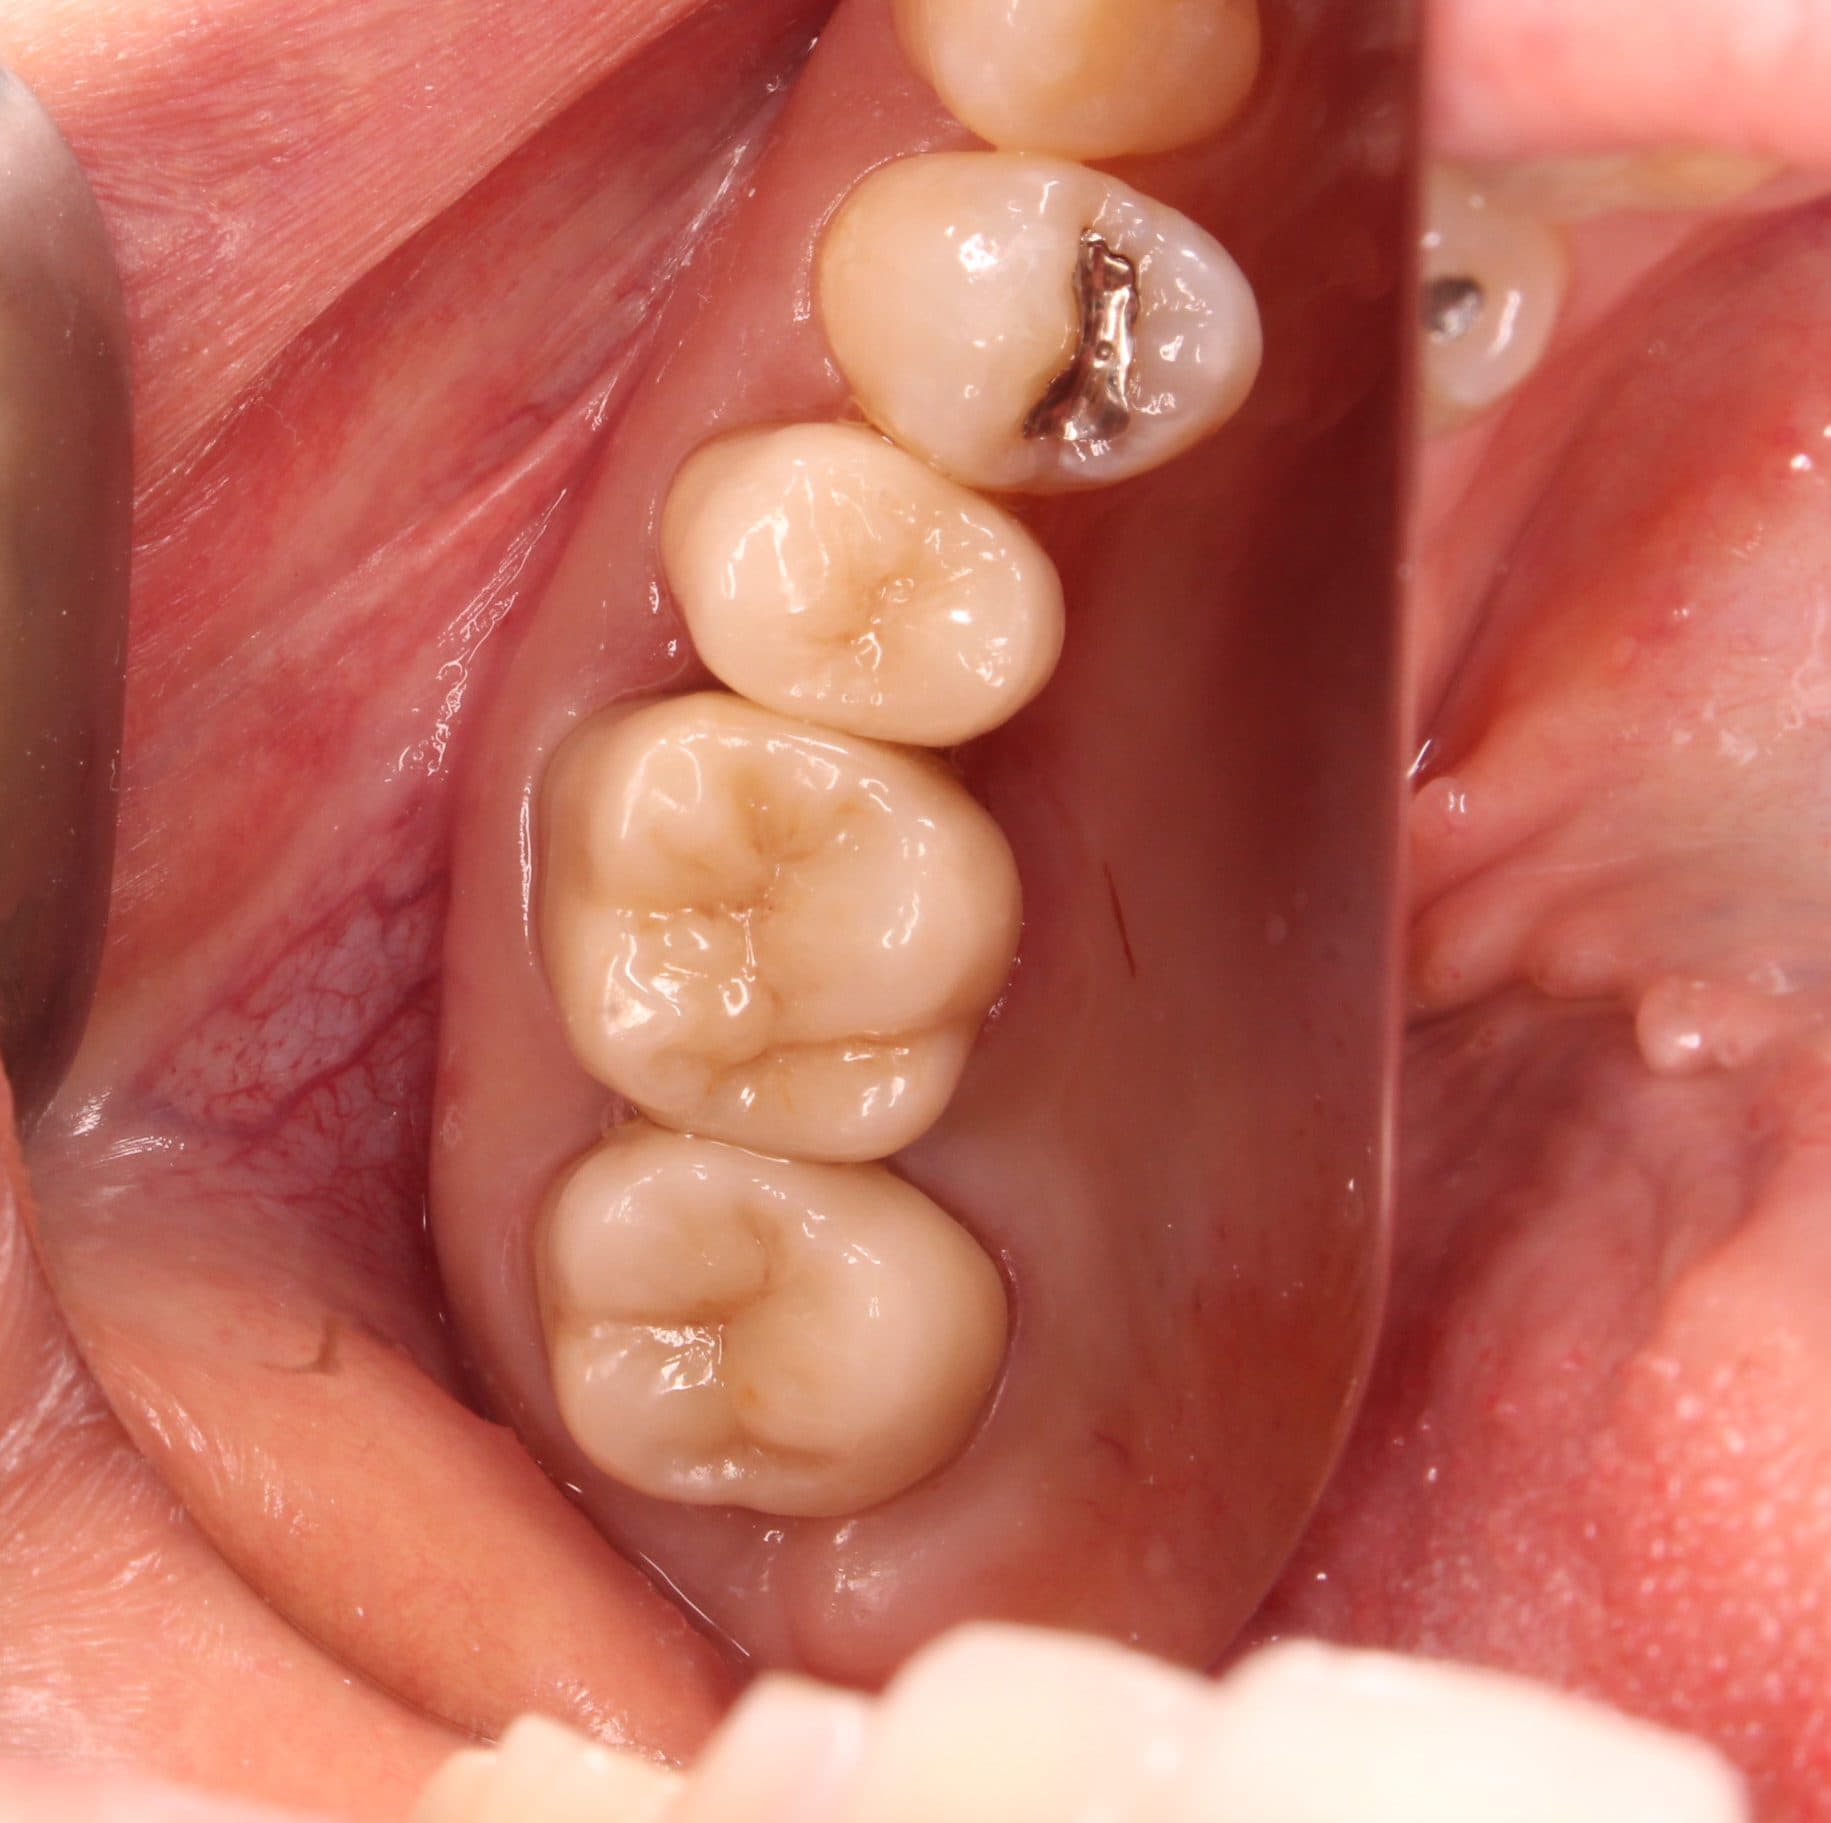

治療後の状態です。

満足して頂きました。

南館歯科クリニックでは、全ての治療において顕微鏡を使用し、精度の高い治療を行っています。

そのため一回の治療時間がどうしても長くなりますが、長持ちさせるためには、どの工程も妥協ができません。